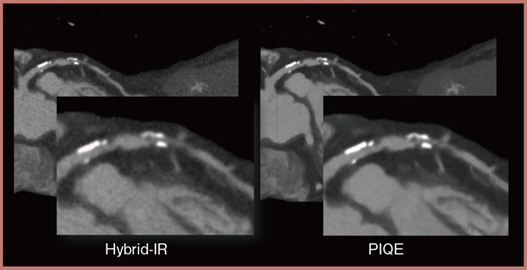

PIQEは,Aquilion PrecisionのSHRモードの画像を教師としてdeep convolutional neural network(DCNN)をトレーニングしたDLRで,ADCTの画像を高分解能化する技術である。PIQEを用いることで,Aquilion ONE / PRISM Editionで撮影した画像がより高精細となり,冠動脈ステントのストラットの構造やステントが重なっている部分の内腔の評価がより詳細に可能となった。従来のCTではアーチファクトによって正確な評価が難しかった石灰化も,PIQEを用いることで分布がより明瞭となり,内膜プラークもより詳細に評価できる(図3)。さらに,不整脈症例においては,PIQEを用いることで,わずか10mLの造影剤量で冠動脈と左心房の明瞭な画像が得られ,アブレーション術前の評価が可能となる。

図3 PIQEによる石灰化プラークの評価